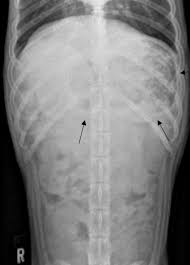

The Causes Of Ascites Fluid In The Abdomen In Dogs Pethelpful from images.saymedia-content.com In cats, the tumors are rarer than in dogs but male cats and siamese breeds are more at risk. Cancer of the digestive system is uncommon, with stomach tumors representing less than 1% and intestinal tumors less than 10% of all cancers in small animals. The presence of blood in the stools, potentially accompanied by mucous. These include masses or tumors, twisting of the intestines around the membrane that separates them from the abdominal. The dog affected by gastric adenocarcinoma may not show any symptoms of the disease. Adenocarcinoma is a malignant tumor originating in the glandular and epithelial tissue (the lining of the internal organs). In some cases, the dog may show signs such as: Unfortunately, one of the most common initial signs of hemangiosarcoma involves sudden collapse due to massive internal bleeding, usually from a ruptured spleen.

Different types of intestinal cancers result in the development of lesions. The most common cancers of the stomach are adenocarcinomas but other histological types have. Vomiting (with or without blood) Some of the potential symptoms of colon cancer in dogs are as follows: Generally, a dog with intestinal cancer exhibits common symptoms such as anorexia, vomiting, bloody diarrhea, weight loss, abdominal pain and tremors, ascites (fluid accumulation in the abdomen) and in some cases severe constipation.

Your dog might eat something they shouldn't. This type of malignant tumor growth can take place in many parts of the body, including the gastrointestinal system of dogs. Vomiting, sometimes blood or undigested or food that is not properly chewed For example, if you touch the dog, he may growl, whine, or snap at you. Most intestinal tumors are in the large intestine (colon and rectum); As cancer can occur in different sites in a dog's body, symptoms of cancer in dogs vary depending on the type and the location of cancer. Bowel cancer in dogs can have different forms, but they all manifest in the same way. Cancer of the digestive system is uncommon, with stomach tumors representing less than 1% and intestinal tumors less than 10% of all cancers in small animals. Generally, a dog with intestinal cancer exhibits common symptoms such as anorexia, vomiting, bloody diarrhea, weight loss, abdominal pain and tremors, ascites (fluid accumulation in the abdomen) and in some cases severe constipation. Occasionally, other medical conditions can cause bowel obstruction in dogs. Other signs of canine abdominal cancer include anemia, lethargy, diarrhea, bloody stool, dark colored stool, loss of appetite, and loss of sleep. Dogs get upset stomachs for many of the same reasons that humans do. The thought of colon cancer is certainly a frightening prospect, but keep in mind there are many noncancerous causes of these symptoms.